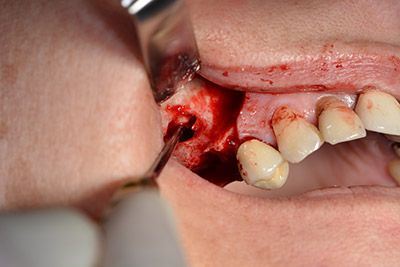

L'incisione classica (rilascio crestale e buccale) e la preparazione del lembo mucoperiosteo favoriscono un'ottima panoramica.

In questo caso vengono usati impianti di tipo SKY (bredent). Il loro protocollo chirurgico specifica una perforazione pilota di circa 1200 rpm (fig. 9).